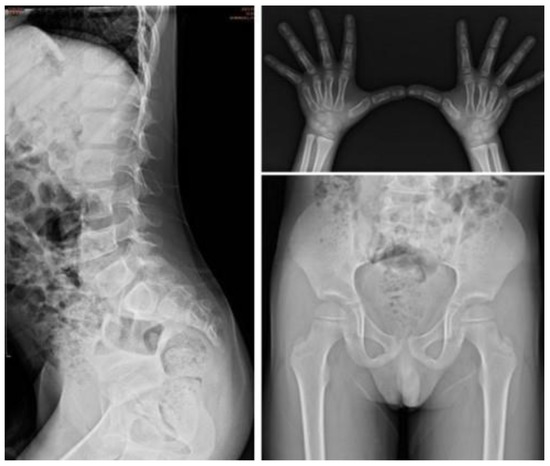

| I-5 | M | c.1400C > T, p.P467L | — | 0.5 | Baseline | 0.2 | 0.27 | 153.16 | 21.4 | 30.01 | 0.11 | Proximal tapering of metacarpal bone with bullet-shaped phalanges. | Normal | Normal | Normal | Normal |

| Follow-up | 3.5 | 7.51 | 18.01 | 0.42 | 3.28 | 2.39 | Suspicious of mild proximal tapering of metacarpal bone with bullet-shaped phalanges. | Multiplex dysostosis of the spine. L-spine vertebral bodies are round. The anterior beaking more at several vertebral bodies of L-spine. | Round iliac wings, inferior tapering of the ilea with not-well developed acetabulum. | Normal | Normal | |||||

| I-6 | M | c.1007–1666_c.1180 + 2113 delinsTT | 0.9 | 0.4 | Baseline | 0.1 | 0.99 | 177.96 | 30.77 | 203.35 | 0.31 | Normal | Normal | Normal | ASD II | Normal |

| Follow-up | 2.8 | 110.92 | 8.9 | 0.1 | 20.64 | 7.05 | Persistent proximal pointed metacarpal and bullet-shaped phalanges of both hands. | Anterior beaking of lower thoracic to lumbar vertebrae. Relative enlargement of sternal end of bilateral clavicles. | Shallow bilateral acetabuli and coxa valga of both femurs. | ASD II, MR, AR | Mild splenomegaly | |||||